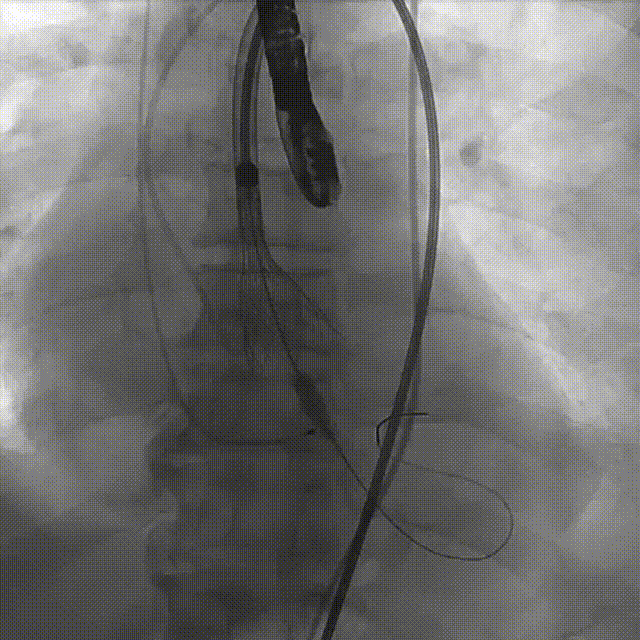

手术过程

主动脉根部造影

导丝跨瓣

20mm球囊预扩

第一次瓣膜释放

第二次瓣膜释放

第三次瓣膜释放

20mm球囊后扩